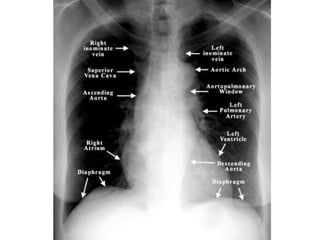

Normal Chest X-Ray

Scheme of viewing PA film

1. Request form                Name ,age, sex, date, clinical information

2. Technical                   View

Centering, patient position

Side Markers

Adequate inspiration

Exposure/Penetrance

3. Soft tissue and bony cage   Subcutaneous emphysema, fractures

4.Trachea                      Position, Outline

5. Heart and Mediastinum       Shape , Size, Displacement

6.Diaphragms                   Outline ,Shape , Relative position

7.Pleural spaces               Position of horizontal fissure,

costophrenic and cardiophrenic angles

8.Lungs                        Local , generalized abnormalities,

comparison of translucency and vascular

marking sof the lungs

9.Hidden areas            Apices, Posterior sulcus, Mediastinum,

Hila, Bones

10. Hila                  Density, Position, Shape

11. Below the Diaphragm   Gas shadows, Calcification